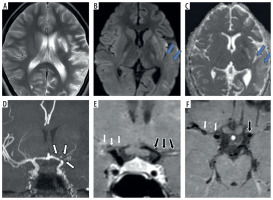

Figure 2

Fifteen-year-old female presenting with right sided hemiparesis. Axial T2 (A), axial diffusion-weighted imaging (B) and axial apparent diffusion coefficient map (C) images show volume loss with mild encephalomalacia in left parieto-occipital region (white arrows in A) along with few areas of diffusion restriction in left temporo-occipital region (blue arrows in B and C). Coronal anterior view maximum intensity projection time-of-flight magnetic resonance angiography (MRA) image (D) shows stenotic left supraclinoid internal carotid artery (ICA) with occluded left terminus ICA and left middle cerebral artery (MCA) (white arrows in D). Coronal post-contrast vessel wall imaging (VWI) (E) and axial post-contrast VWI (F) showing vessel wall thickening and grade 1 concentric enhancement of left supraclinoid, terminus ICA, left MCA and anterior cerebral artery (black arrows in E and F). Grade 1 concentric enhancement is also noted in right supraclinoid, terminus ICA and right MCA (white arrows in E and F)